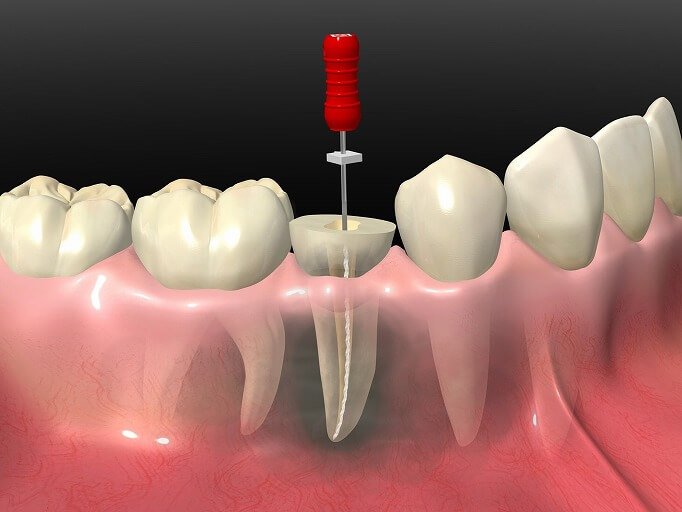

根管治療

根管治療とは、虫歯が神経にまで到達したときに神経を除去する、あるいは一度根管治療された歯において、何らかの理由で感染した根管を再治療することです。

根管治療とは、虫歯が神経にまで到達したときに神経を除去する、あるいは一度根管治療された歯において、何らかの理由で感染した根管を再治療することです。

虫歯が神経まで到達すると、冷水痛、温水痛、自発痛などの痛みを伴います。そのため、神経を除去し、根管内を清掃、殺菌した上で薬剤を充填し、歯の保存を行います。

根管治療後には、被せ物を装着し、その審美性と機能性を回復させます。

CTによる精密な診断

根管は、非常に複雑な形をしています。手技のみに頼っていては確実な治療ができません。当院では、CT検査で根管の状態を3次元的に把握し、診断に役立てるとともに、正確な治療につなげています。

根管は、非常に複雑な形をしています。手技のみに頼っていては確実な治療ができません。当院では、CT検査で根管の状態を3次元的に把握し、診断に役立てるとともに、正確な治療につなげています。

また、複雑な根形態の場合のCT撮影は保険適用となりますので、随時お伝え致します。

ラバーダムを使用し、

細菌感染を防止

根管治療では、根管を徹底的に清掃・殺菌した上で、薬剤を充填しなければなりません。少しでも唾液が入ってしまうと、唾液中の細菌によって後から感染を起こしてしまうためです。

根管治療では、根管を徹底的に清掃・殺菌した上で、薬剤を充填しなければなりません。少しでも唾液が入ってしまうと、唾液中の細菌によって後から感染を起こしてしまうためです。

当院では、治療をする歯だけを露出させるラバー製のシート「ラバーダム」を使って、根管治療中の細菌の感染を防いでいます。精密な根管治療には、欠かせないひと手間です。